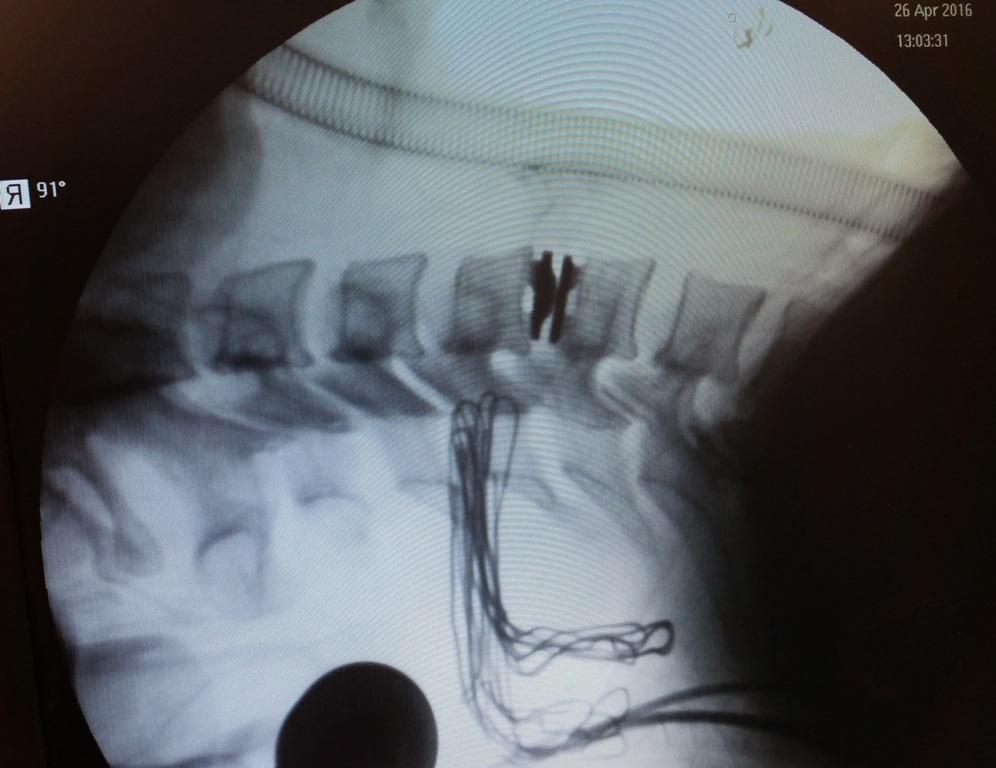

REBORN CORPECTOMY IMPLANTS & MESH

Corpectomy Reborn® Corpectomy Implant system consists of expandable Corpectomy Implant, cages and me...